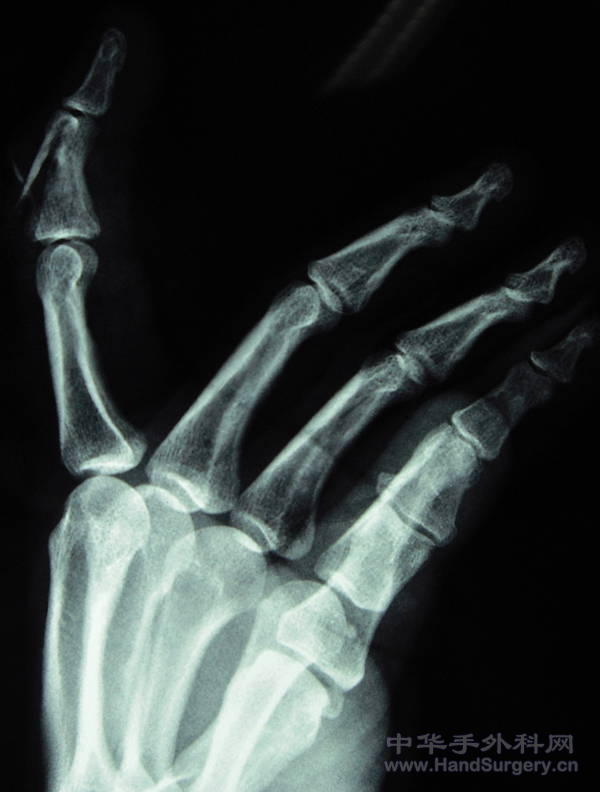

骨折你这样内固定还敢做这个筋膜瓣,真厉害,希望你把术后成活的照片补上来!谢谢!

我看那个创面皮肤成锯齿状血运应该很好。好像没有缺损吧。不可以真接缝上吗。。我们这边锣刀割伤的比这还碎,一般成活都没问题。再说底下是钢板,再铺筋膜蒂植皮打包风险比较高吧。还不如做同指的筋膜蒂皮瓣。个人愚见。

呵呵,如果你不是选择上钢板的话,可能可以直接缝合了,筋膜瓣加植皮易引起挛缩,另外这个钢板放在这里是不是会影响伸指肌腱的功能啊,楼主应加强随访!皮瓣切取思路不错的,学习了

好像还打克氏针了,得克氏针+可吸收线或钢丝就能解决问题,